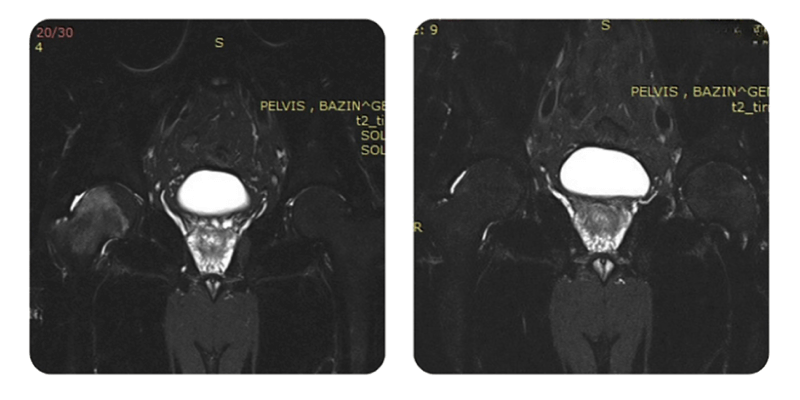

Prima

Dopo

Evoluzione: Dopo 20 sedute, il paziente riferisce miglioramento significativo del dolore; nell'ultima settimana ha osservato una lieve riacutizzazione. Le sedute sono state ben tollerate e la valutazione di imaging indica un miglioramento di circa l'80-90%.

Al controllo, il paziente si presenta senza dolore. La RMN di controllo a 1 anno mostra quadro stabile, senza edema osseo, con buone condizioni generali.

La RMN di controllo a 1 anno il quadro risulta stabile, senza edema osseo, con buono stato generale.